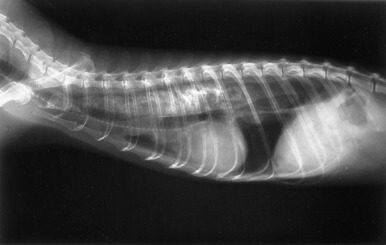

How do you diagnose that they have eaten something ‘foreign’?

We start by giving the ferret a thorough clinical examination. If they are showing some of the symptoms of foreign body ingestion then radiographs (x-rays) or an ultrasound may be recommended. This allows us to see if and where a foreign object may be lodged.